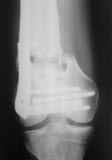

Больной, 30 лет, высокоэнергетическая травма 6 мес назад (базальный перелом шейки бедра + перелом дистального метаэпифиза бедра на той же ноге по типу 33-С2). Практически сразу же был произведен МОС шейки системой DHS (Synthes), через две недели - МОС дист.отдела бедра системой LISS (Synthes)плюс костная пластика с крыла подзвдошной кости.

На сегодняшний день наступил перелом пластины, укорочение бедра 2 см. Перелом шейки клинически и рентгенологически сросся. Больной астеничен, немного анемичен. Рентгенограммы прилагаются.